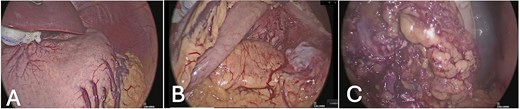

Given progressive anemia and recurrent bleeding, the patient underwent total gastrectomy with Roux-en-Y esophagojejunostomy, distal pancreatectomy, splenectomy, and segmental resection of the transverse colon with mechanical end-to-end anastomosis. The procedure began laparoscopically and revealed a 10 cm tumor between the spleen and pancreatic tail, eroding the serosa of the greater curvature and invading the transverse colon. Dissection proceeded with mobilization of the greater curvature, the hepatoduodenal ligament, and the pancreatic head (Fig. 2). Due to colonic invasion, conversion to open surgery was required to complete the colectomy and reconstruction. Estimated blood loss was 800 ml, and intraoperative peritoneal lavage cytology was negative for malignant cells.

Intraoperative laparoscopic views: (A) stomach in situ before dissection; (B) exposure after mobilization of the greater curvature; (C) dissection of the hepatoduodenal ligament and pancreatic head.